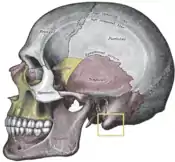

The external ear (pinna) is a surgically-challenging area in terms of anatomy, composed of a delicate and complex framework of shaped cartilage that is covered, on its visible surface, with thin, tightly adherent, hairless skin. Although of small area, the surface anatomy of the external ear is complex, consisting of the pinna (the auricle) and the external auditory meatus (auditory canal). The outer framework of the pinna is composed of the rim of the helix, which arises from the front and from below (anteriorly and inferiorly), from a crus (shank) that extends horizontally above the auditory canal. The helix merges downwards (inferiorly) into the cauda helices (tail of the helix), and connects to the lobule (earlobe). The region located between the crura (shanks) of the antihelix is the triangular fossa (depression), while the scapha (elongated depression) lies between the helix and antihelix. The antihelix borders in the middle (medially) to the rim of the concha (shell) and the concha proper, which is composed of the conchal cymba above (superiorly) and the conchal cavum below (inferiorly), which are separated by the helical crus, and meet the antihelix at the antihelical rim. The tragus (auditory canal lobule) and the antitragus (counterpart lobule) are separated by the intertragal notch; the auditory canal lobule does not contain cartilage, and displays varied morphologic shapes and attachments to the adjacent cheek and scalp.

Protruding mastoid process

Auricular prominence

The occurrence of a prominent mastoid process tends to push the concha forward, which extends the pinna (external ear) away from the side of the head. The external ear is mounted upon the bony base of the underlying temporal bone, therefore, anomalies and asymmetries of the skeletal shape can cause either pinna, or both pinnae, to become prominent. In relation to the protruding mastoid process, the most recognizable skeletal anomaly is the change in the position and in the projection of the pinna, as associated with non-synostotic plagiocephaly (the positional flattening of the side of the head, not caused by the inappropriate union of two bones). Hence, in the occurrence of a flattening of the skull (parallelogram deformation of the cranial vault), the side of the head afflicted with occipital plagiocephaly presents a prominent ear. In subtle cases, the prominent ear might be more readily evident in an elder patient, whose ears are asymmetrically positioned, reason for which the residual occipital flattening (occipital plagiocephaly), and mild facial asymmetry, are unapparent at first view. This effect, of the shape of the patient's head, upon the outward and extended position of the ear is notably indicated in the 1881 illustrations that describe the Ely otoplasty technique.